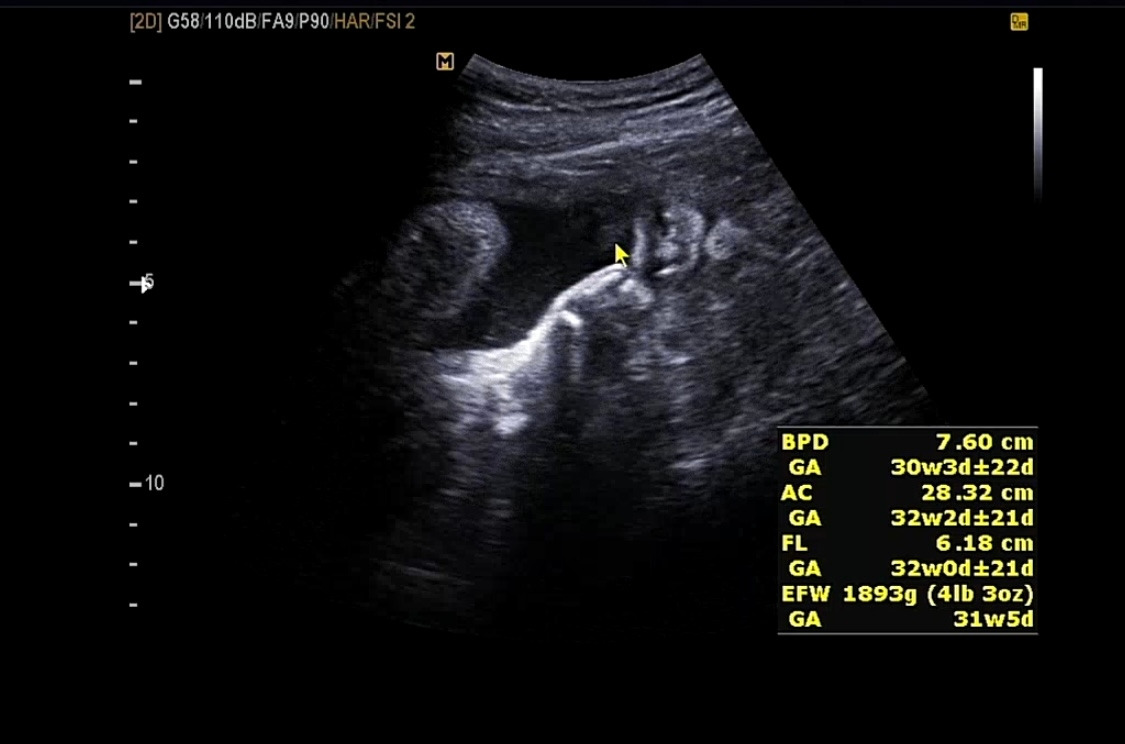

그 사이 궁금해서 남편과 함께 다른 병원을 방문했었다. 너무 오랫동안 다올이를 못 봤었기 때문에 얼마나 컸는지 궁금하기도 했고 어차피 백일해 주사를 맞으러 다른 병원을 갈 예정이었기 때문에 겸사겸사 다올이와 인사하고 왔다.

그사이 열심히 커버린 우리 다올씨

기특하다 기특해

자궁 구석에 콕 박혀있는 다올이는 얼굴을 잘 보여주지 않았고,

잠깐 얼굴을 볼 수 있었다.